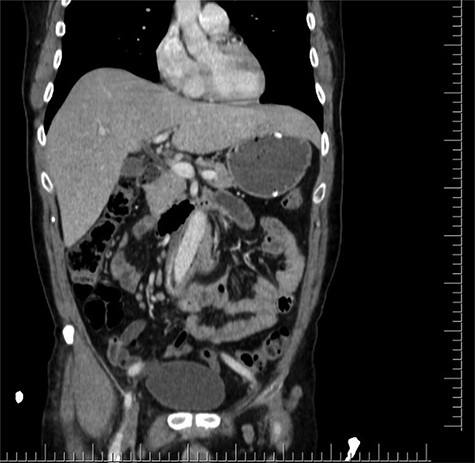

During the first days of December 2018, the patient visited another medical center because of fatigue, difficulty in breathing, lower back pain and inability to walk. His blood biochemistry revealed a very high CRP level (350 mg/dl), and complete blood count revealed a very high level of white blood cells (21 000/ul). An abdominal CT scan illustrated part of the graft was totally eroded into the small intestine (Figs 1–3). The patient was referred to my office and an infectious disease specialist. He had high body temperature (39.5°C) and was lying on the bed with lower extremities adducted to the chest. Antibiotic and supportive treatment was started. Emergency surgery was performed. We found an 8–10 cm of the straight part of the graft had become totally incorporated into the proximal part of the jejenum. The graft was freed, and 10–15 cm of the jejenum was resected and anastomosed. The area was irrigated with saline and hypochlorous acid. We then put a 20 x 10 composite mesh between the vascular graft and the intestine using a non-adhensive surface facing the intestine to prevent future graft and intestine interactions and erosion. After hemostasis, two drains were placed retroperitonally, and the abdomen was closed. On the fourth post-operative day, a high body temperature and high CRP levels were recorded. An abdominal CT revealed retroperitoneal abcess formation. During relaparotomy, the anastomosis was found to be intact, and the retroperitoneal abscess was drained and irrigated with saline. The drains were reinserted. After a month, he once again started to have high fever and high CRP levels. Again, an abdominal CT revealed abscess formation. This time, the abscess was approached transcutaneously. By making an incision in the proximal left lomber region, the abscess was drained. Another incision was made distally, and two drains were placed in the retroperitoneal area.

Coronal CT section shows straight part of the Dacron graft in the jejenum.